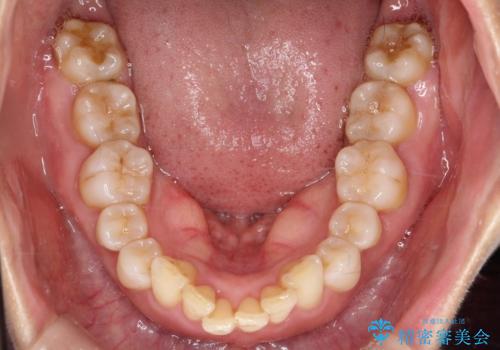

- 前歯が出ていることを主訴に来院されました。

インビザラインにて臼歯部の遠心移動及びIPRを行なっています。

叢生量が多いケースでしたが、綺麗な歯並びとなり患者様にも満足していただきました。